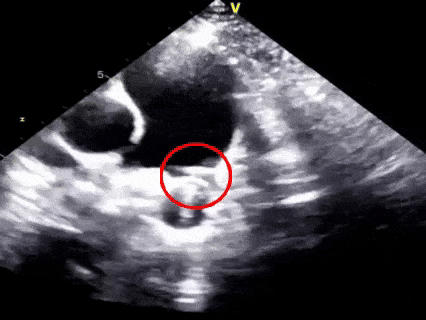

三“锁”,成型锁定

多切面确认封堵器形态良好,一侧在肺动脉一侧在主动脉

胸骨旁主动脉短轴切面

胸骨上窝主动脉弓长轴切面